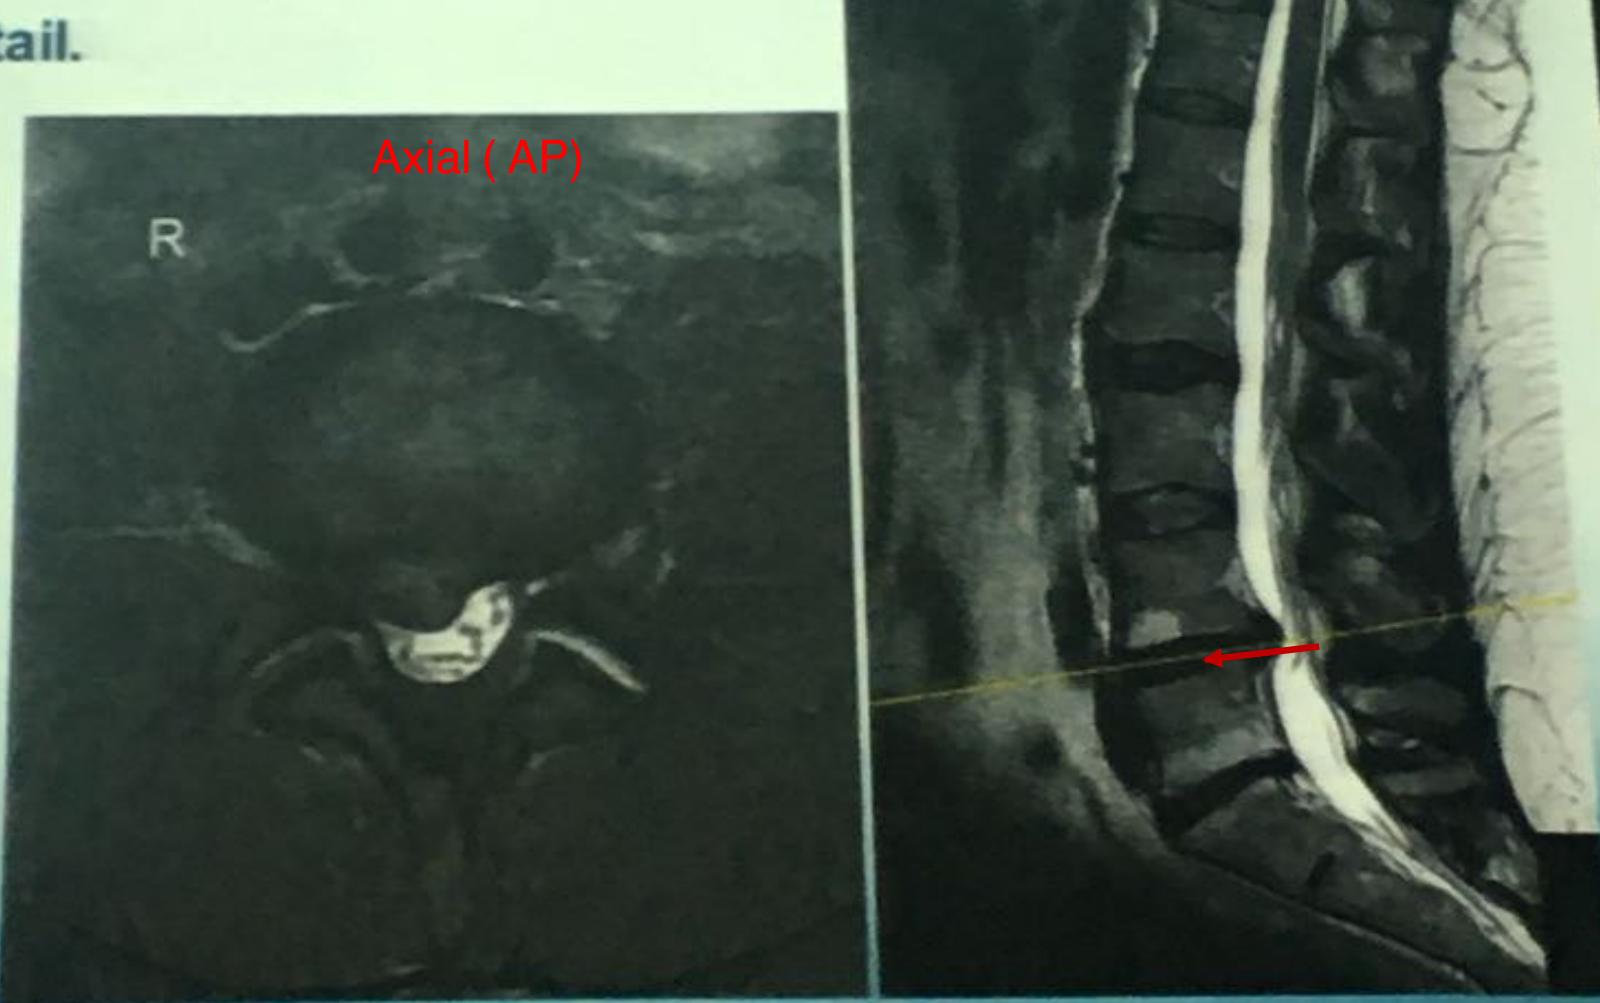

This patient has back pain radiating down to his right leg. examine the back

| Straight leg raise (Lasègue test) | In supine position, raise leg up with knee straight. Look and ask for pain. When pain starts, reduce leg raise, pain disappears. Now passively dorsi-flex ankle to reproduce pain. | ![]() | |